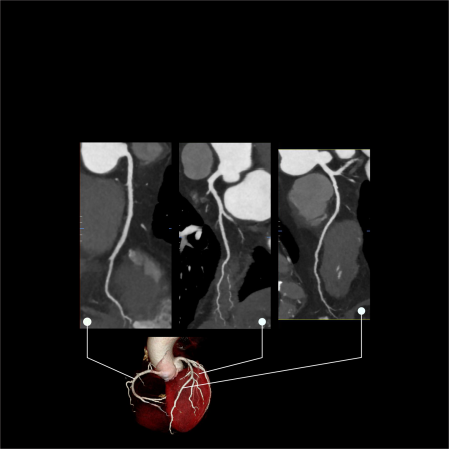

Coronary angiography

Illustrations for clear understanding

Real scan images